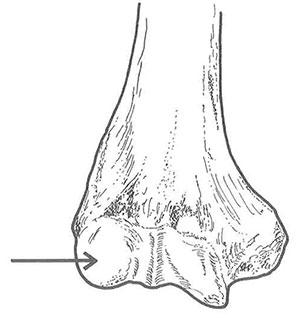

上腕骨遠位部の図を示す。矢印の部位はどれか。

1

肘頭窩

2

外側上顆

3

鈎状突起

4

内側上顆

5

上腕骨小頭